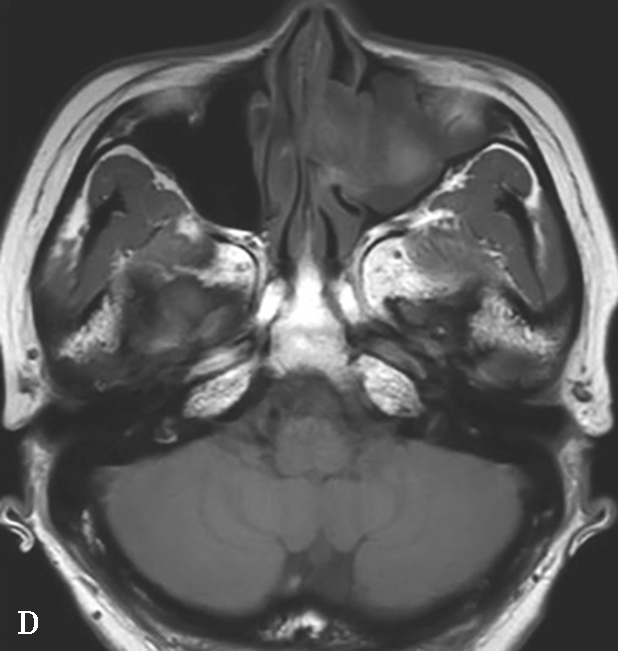

①平扫表现:受累鼻窦窦腔不均匀实变,病变中央可见点、细条或云絮状高密度影,融合成团块状,密度高于软组织但低于骨质,平均CT值约140HU,由真菌菌丝中的钙盐、铁和镁等重金属形成。窦壁骨质增生伴骨质破坏,骨质破坏多见于近上颌窦自然开口处(图1-3-21A~C)。②增强扫描表现:边缘黏膜明显强化。

5.MRI表现

①T 1 WI表现:真菌菌丝呈低信号或等信号;外周黏膜炎症为中等信号。②T 2 WI表现:呈极低信号,甚至无信号;外周黏膜呈高信号。③增强扫描表现:真菌菌丝无强化,边缘黏膜明显强化(图1-3-21D~F)。

图1-3-21 真菌球

A~C.横断面CT骨窗、横断面软组织窗、冠状面CT骨窗,A、C示左侧上颌窦内充填软组织密度影,伴中央多发条状、云絮状高密度影,上颌窦窦口扩大,窦壁骨质增生硬化、肥厚;B示窦腔实变,中央高密度影显示更清楚;D~F.MRI横断面T 1 WI、T 2 WI及增强T 1 WI,示左侧上颌窦内软组织影,T 1 WI呈等、高信号,T 2 WI呈等、高信号,窦口区病变T 1 WI呈不规则形等、稍高信号,T 2 WI呈极低信号,增强扫描后窦口区病变无强化,周边黏膜呈线样强化